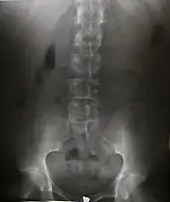

Radiography is an imaging technique using X-rays, gamma rays, or similar ionizing radiation and non-ionizing radiation to view the internal form of an object. Applications of radiography include medical radiography ("diagnostic" and "therapeutic") and industrial radiography. Similar techniques are used in airport security (where "body scanners" generally use backscatter X-ray). To create an image in conventional radiography, a beam of X-rays is produced by an X-ray generator and is projected toward the object. A certain amount of the X-rays or other radiation is absorbed by the object, dependent on the object's density and structural composition. The X-rays that pass through the object are captured behind the object by a detector (either photographic film or a digital detector). The generation of flat two dimensional images by this technique is called projectional radiography. In computed tomography (CT scanning) an X-ray source and its associated detectors rotate around the subject which itself moves through the conical X-ray beam produced. Any given point within the subject is crossed from many directions by many different beams at different times. Information regarding attenuation of these beams is collated and subjected to computation to generate two dimensional images in three planes (axial, coronal, and sagittal) which can be further processed to produce a three dimensional image.

Since the body is made up of various substances with differing densities, Ionising and non-ionising radiation can be used to reveal the internal structure of the body on an image receptor by highlighting these differences using attenuation, or in the case of ionising radiation, the absorption of X-ray photons by the denser substances (like calcium-rich bones). The discipline involving the study of anatomy through the use of radiographic images is known as radiographic anatomy. Medical radiography acquisition is generally carried out by radiographers, while image analysis is generally done by radiologists. Some radiographers also specialise in image interpretation. Medical radiography includes a range of modalities producing many different types of image, each of which has a different clinical application.

Projectional radiography

The creation of images by exposing an object to X-rays or other high-energy forms of electromagnetic radiation and capturing the resulting remnant beam (or "shadow") as a latent image is known as "projection radiography." The "shadow" may be converted to light using a fluorescent screen, which is then captured on photographic film, it may be captured by a phosphor screen to be "read" later by a laser (CR), or it may directly activate a matrix of solid-state detectors (DR—similar to a very large version of a CCD in a digital camera). Bone and some organs (such as lungs) especially lend themselves to projection radiography. It is a relatively low-cost investigation with a high diagnostic yield. The difference between soft and hard body parts stems mostly from the fact that carbon has a very low X-ray cross section compared to calcium.